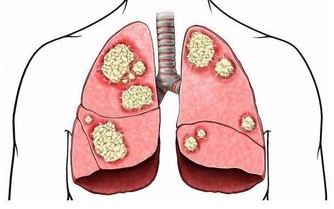

血液中的「血垢」是指膽固醇、甘油三酯等,它們在血管壁上越積越多,形成如同黃色小米粥樣的斑塊。

很多人以為,只有到老了的時候,才為我們的血管操心。殊不知,血管斑塊變大,從30歲以後就加速了。